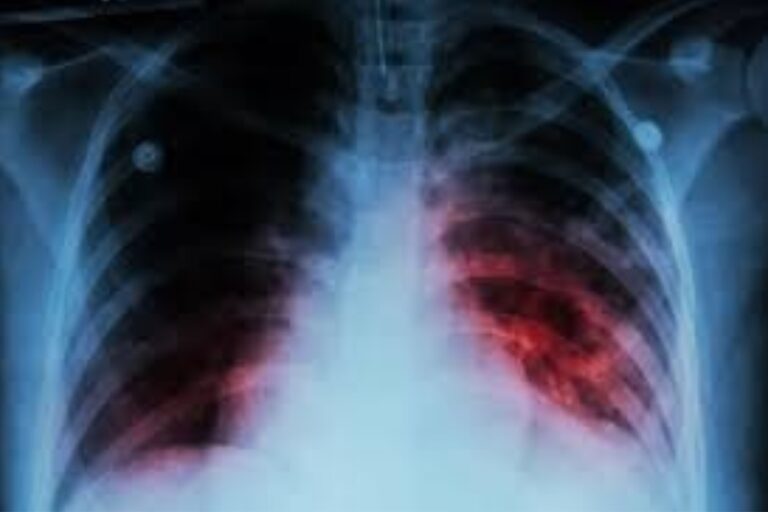

La tuberculosis continúa siendo una de las principales causas de muerte por agentes infecciosos a nivel mundial, con más de 10 millones de casos y 1,2 millones de fallecimientos notificados en 2024. En la Región de las Américas, se registraron aproximadamente 350.000 personas con tuberculosis en 2024, el mayor número registrado desde que se disponen de datos, y un aumento del 13% en la tasa de incidencia respecto a 2015.

La publicación de esta nueva edición de la guía se inscribe en un contexto epidemiológico nacional que requiere actualizar y unificar estrategias de abordaje. Argentina registra un aumento sostenido de tuberculosis desde hace 5 años, alcanzando 17.283 casos en 2025 y una tasa de incidencia de 37,3 casos cada 100.000 habitantes. Este aumento se produjo a expensas de unidades territoriales específicas. Buenos Aires y la Ciudad Autónoma de Buenos Aires concentraron el 66,1% del total nacional en 2025, pero la mayor tasa de incidencia se registró en Salta con 60,5 casos nuevos por 100.000 habitantes y 55,7 de casos incidentes. Por otro lado, también se identificaron 14 sub jurisdicciones donde la tuberculosis mantiene una presencia persistente, aun cuando no presentan un aumento estadísticamente significativo. Estas áreas se localizan principalmente en PBA, CABA, Formosa, Jujuy y Salta.